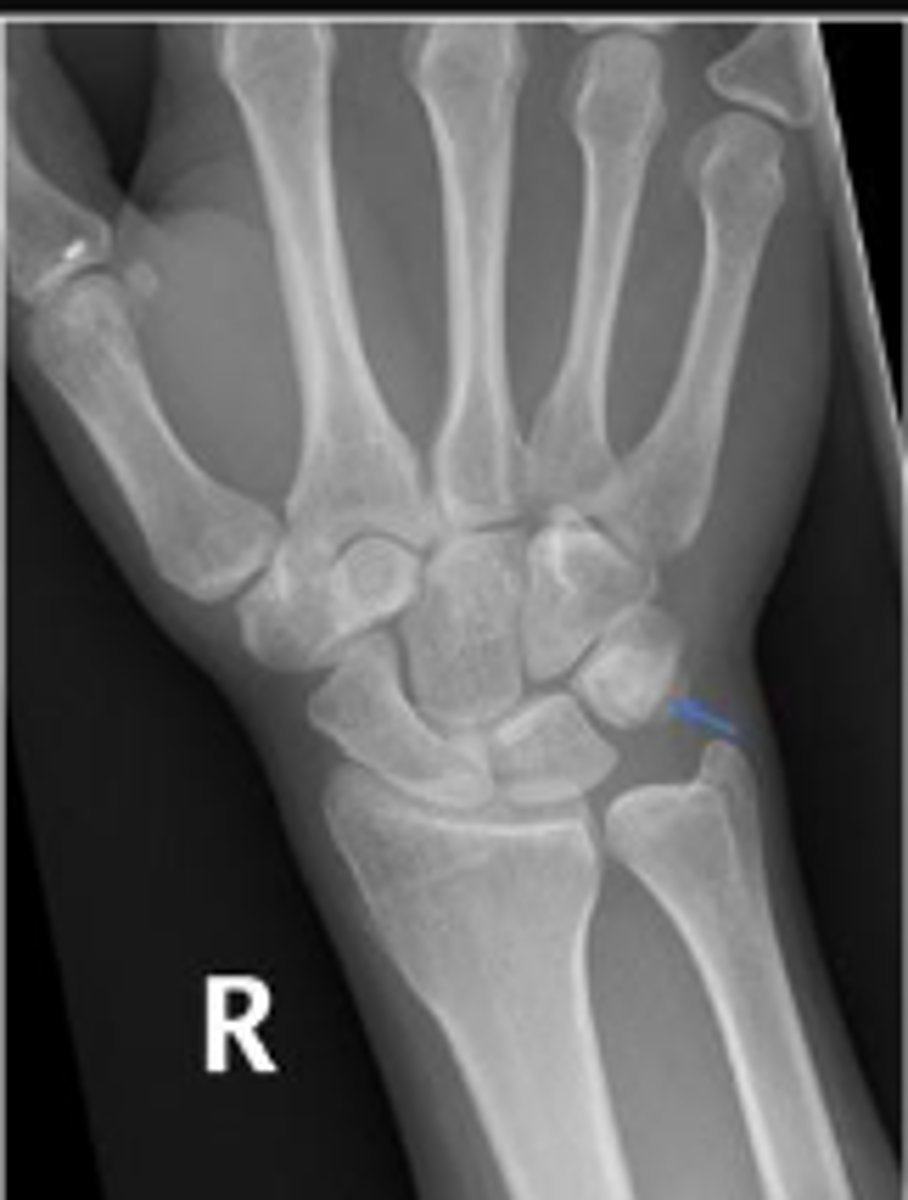

PA of the left wrist

What is the name of the radiographic view?

Left pisiform

What is the arrow pointing to?

Left capitate

Right radiocarpal joint

What joint space are the arrows pointing to?